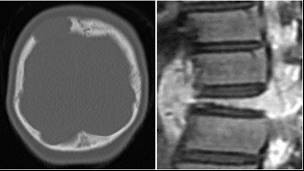

骨病変

頭の骨に最も多くみられます。あばら骨や腰骨、背骨、あごの骨、手足の骨にもみられます。頭の骨の場合、こぶのように腫れてぷよぷよとし、その後、中心部がへこんでクレーターのような状態になります。頭をぶつけたところからでてくることがあります。足や骨盤の骨の場合、痛みで足を引きずることがあります。顎の骨の場合、歯が抜けることがあります。背骨の場合、骨の周りが腫れて神経を圧迫しヘルニアのような症状がでることがあります。目の周りの骨の場合、目がとび出たり視力がおちたりすることがあります。単純レントゲンでは骨が融けたようにみえます。打撲した部位に病変が生じることがあります。

肺病変

成人では肺だけに病変がある患者さんがあり、検診などでたまたま見つかることがあります。成人の患者さんのほとんどは喫煙者です。子どもでは、ほとんどが多臓器型で肺が病変のみという患者さんはありません。自覚症状としては、乾いた咳、息切れ、息苦しさです。肺が破壊されると、肺が空気のふくろにおきかわり、それが破れると、肺と胸の壁の間に空気が漏れて肺が縮んでしまう、すなわち気胸をおこします。さらに肺の破壊が進むと、空気のふくろだらけ、すなわち蜂巣様肺となり、息ができなくなることがあります。